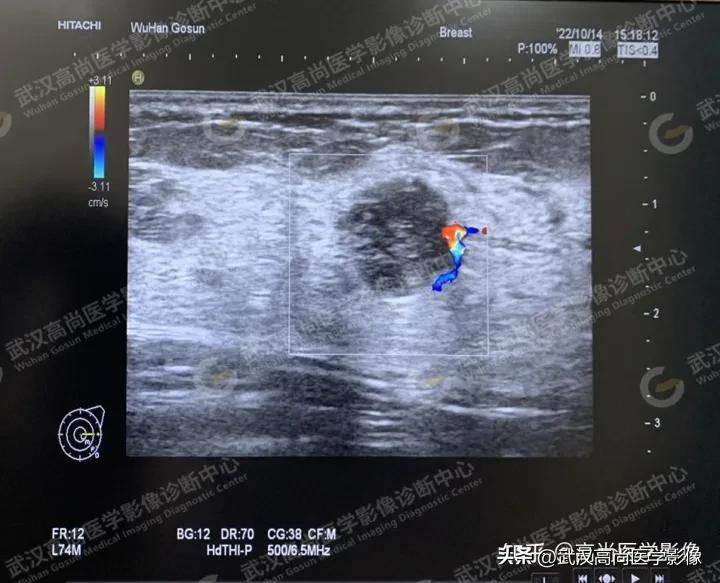

患者二:

女、24 岁,于本中心体检,发现乳腺结节,主诉有乳腺癌家族史,余无不适。

超声图像如下:

图一、图二、图三、图四:左侧乳腺1点方向低回声结节,边界尚清,轮廓不规整,多个方向成角,内回声不均匀,边缘见丰富血流信号RI=0.74